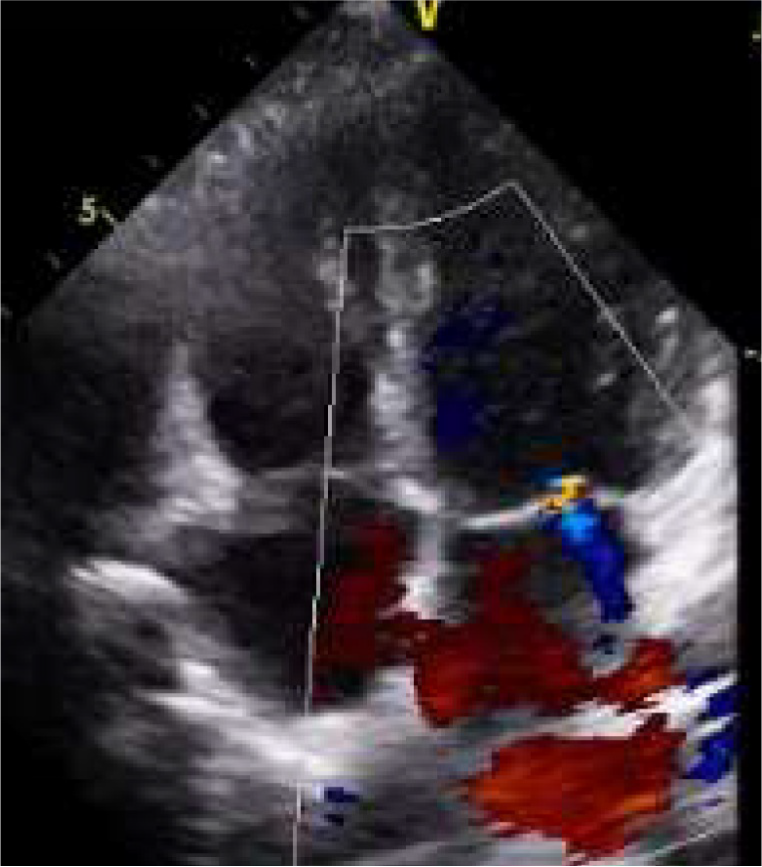

・心エコー

心臓の動き、弁膜症、心不全の兆候を評価します。